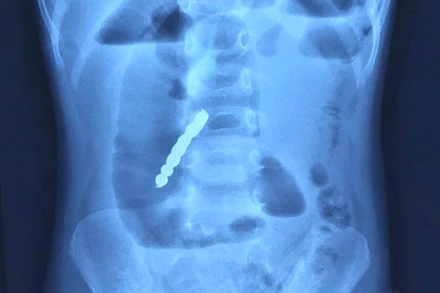

Vừa qua, các bác sĩ Bệnh viện Nhi Trung ương đã phẫu thuật cấp cứu cho bé gái N.P.T (2 tuổi, ở Bắc Ninh) bị thủng ruột do nuốt phải bảy viên bi nam châm.